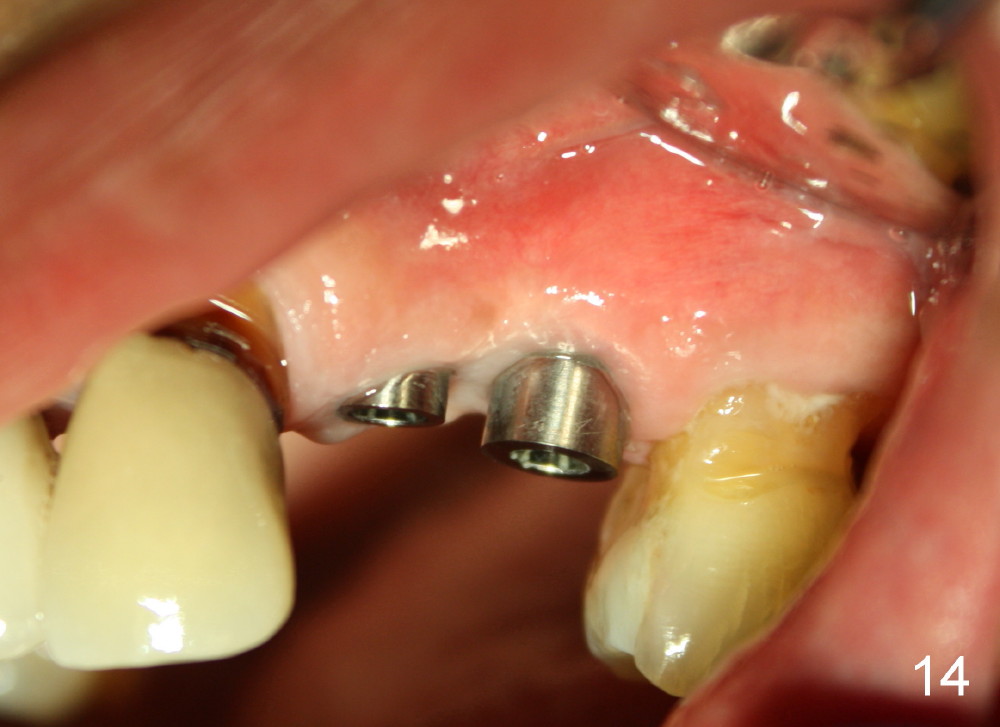

Three month follow-up shows that the gingiva and bone heal around these two implants (Fig.13-15).  Crowns are cemented 4.5 months postop (Fig.16).  There is no or minimal bone loss 9 months post cementation (Fig.17, as compared to Fig.15).  The bone is stable around the implants 18 months post cementation (Fig.18 panoramus).  Root canal therapy is done at #14 between the last follow up appointments.